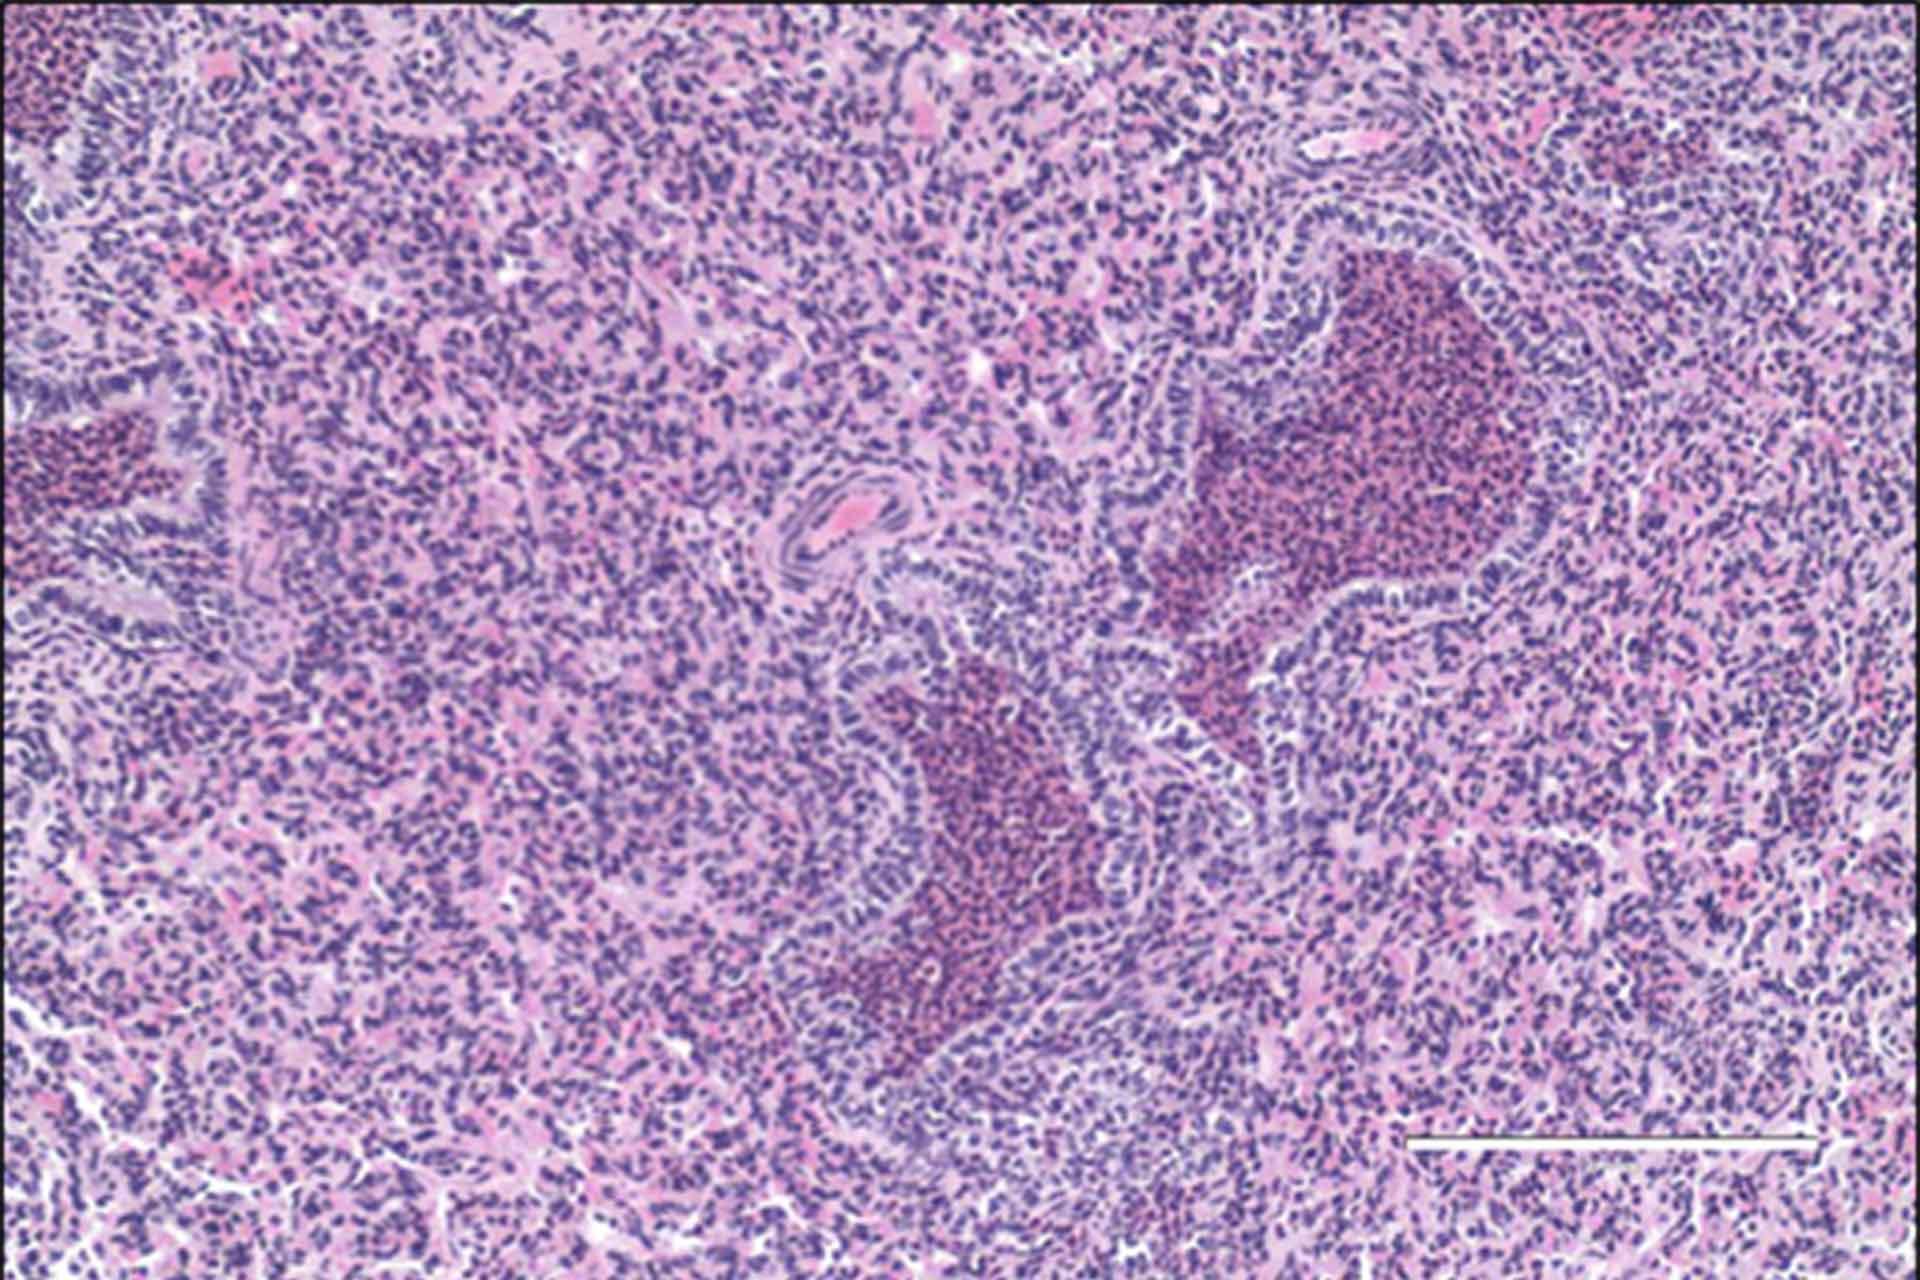

Pigs that were treated with one of the mAbs prior to infection were protected from severe disease and the flu virus was eliminated from their lungs. “These results indicate that the mAbs have therapeutic potential and could be used to evaluate mAb delivery methods” added Dr Tchilian.